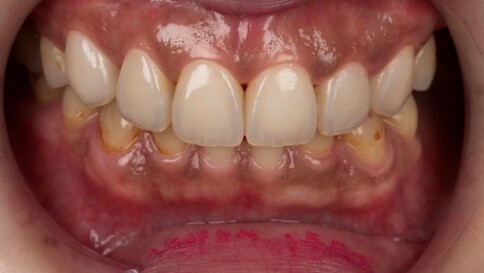

當您只有「單顆」門牙受損時,挑戰在於模仿隔壁那顆「天生的牙」。我們利用全瓷冠的高透光性創造視覺平衡,避免做出一顆看起來很新卻很突兀的假牙。

Case 1:舊假牙死白換新,牙肉回彈跡象。